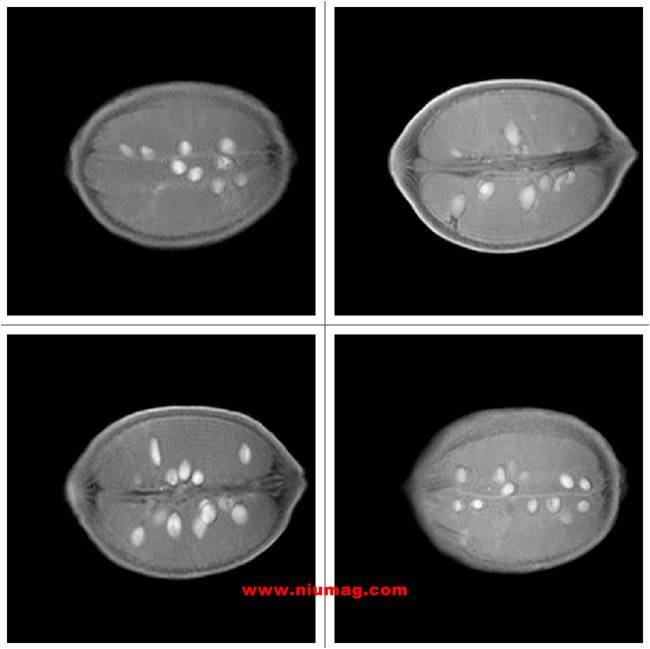

玉米核磁共振多層成像圖-橫斷位